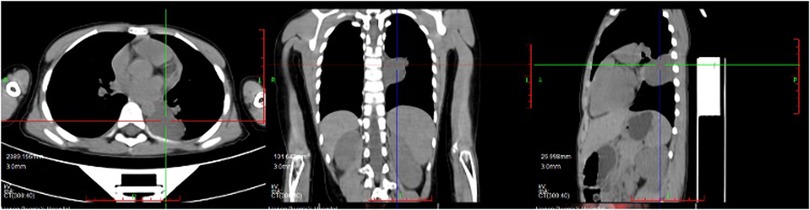

An 8-year-old boy presented with a one-week history of intermittent left-sided chest pain, bloating, and nausea. On physical examination, all findings were within normal ranges except for left chest tenderness and slightly restricted respiratory movements. Preoperative imaging included chest radiography, US, and PET/CT. The chest radiograph demonstrated a high-density mediastinal shadow, while US identified a 55*48*37 mm posterior mediastinal mass in the suprasternal region (Figure 1). Subsequent PET/CT further characterized a 37*31*37 mm paraspinal cystic lesion in the left lower lobe with loss of metabolism, confirming the need for surgical resection (Figure 2). Laboratory studies indicated no contraindications to surgery.

Figure 2. Preoperative PET/CT indicated paraspinal cystic lesion in the left lower lobe with loss of metabolism.